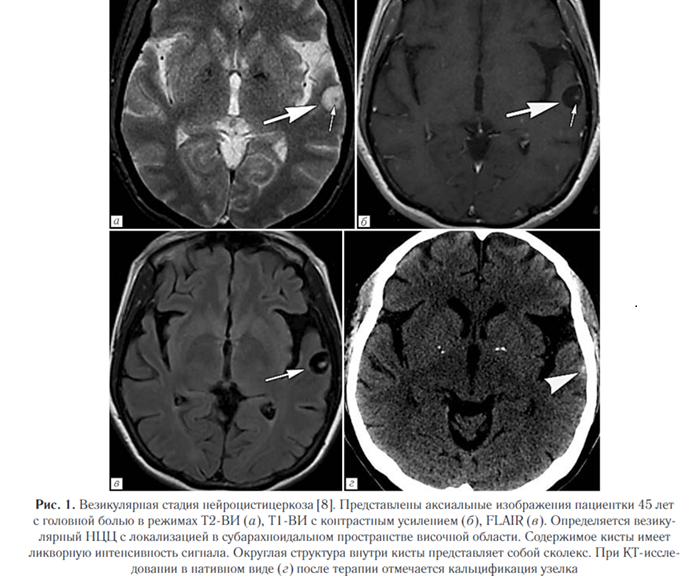

2. Везикулярная стадия (активная). Визуализи - руется полностью выросшая киста или скопление кист (по типу «грозди винограда») в базальных ганглиях, мозжечке, стволе мозга, цистернах или желудочковой системе, в паренхиме полушарий и в субарахноидальных пространствах. Сколекс встречается почти в 50% случаев. НЦЦ по типу «грозди винограда» наблюдается обычно вокруг рострального ствола мозга или сильвиевой щели, обычно лишен сколекса. Отек практически отсутствует (рис. 1).

5. Кальцифицированная узловая стадия (неактивная) чаще всего проявляется в виде гранулематозного поражения, которое инволютировалось и полностью кальцинировалось (рис. 3). Нейровизуализация является очень важным методом диагностики НЦЦ в связи с тем, что позволяет визуализировать цистицерки, оценить их распространенность и локализацию в ЦНС [2]. КТ обладает высокой чувствительностью и специфичностью при большинстве форм НЦЦ и превосходит МР-визуализацию в выявлении кальцинированных гранулем. Однако внутрижелудочковые кисты могут быть трудно идентифицированы с помощью КТ из-за аналогичной плотности ликвора и жидкости кисты.